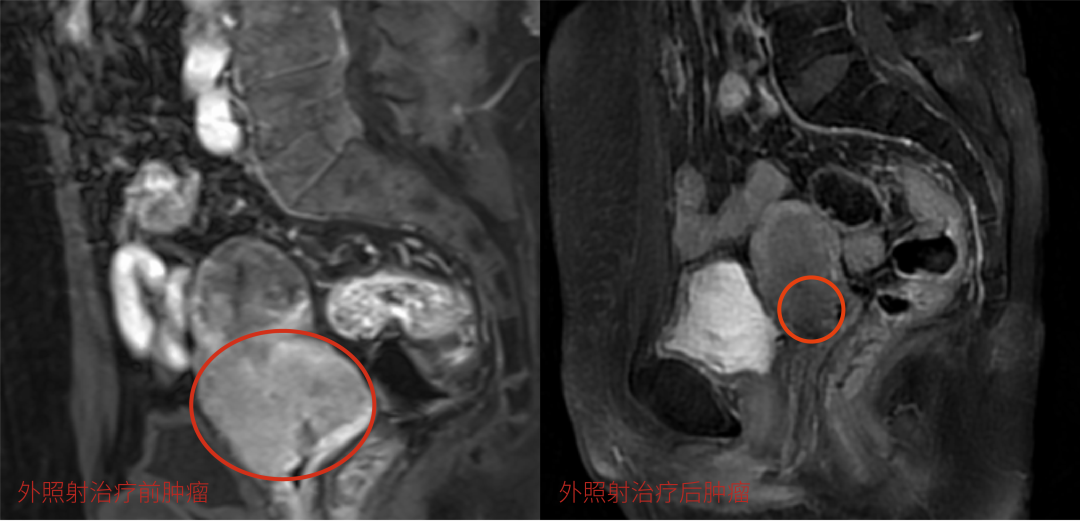

经过前两步的治疗,效果已初显,李阿姨腹部的下坠疼痛感消失,宫颈也不出血了。复查结果显示:鸡蛋大小的宫颈肿瘤已经缩小,盆腔转移的淋巴结也得到了很好的控制。

诱导化疗+外照射核磁共振前后对比:肿瘤明显缩小